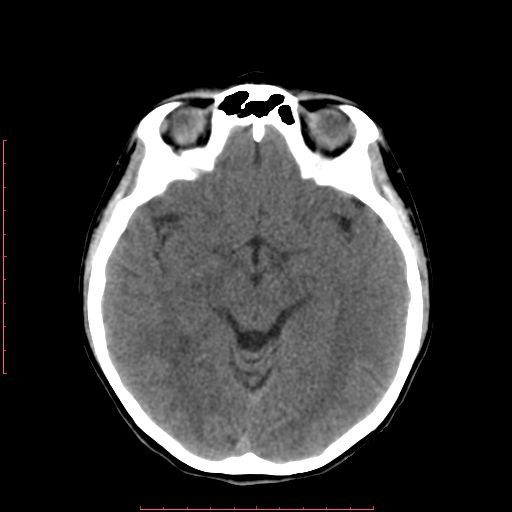

白色文字(排除指定关键词) Imaging Anatomy: interactive PACS-like atlas of radiological anatomy

解剖学模块